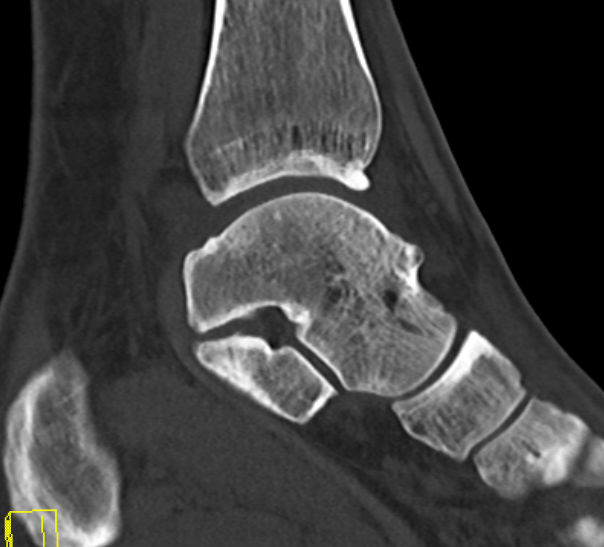

CT

Anterior tibial and talus spurs with normal joint space